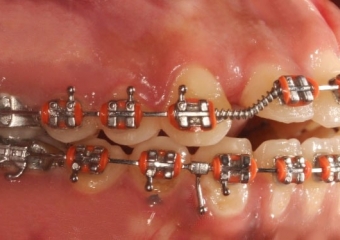

Mordida após a cirurgia  - Clínica Cliniface

Mordida após a cirurgia